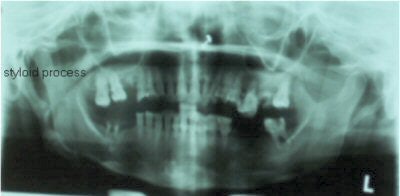

OPG x-ray shows presence of bilateral elongated styloid processes. On the right side, the stylohyoid process is calcified/ossified. Pseudoarticulation of the stylohyoid ligament is seen extending up to the anterior-superior border of the hyoid bone.